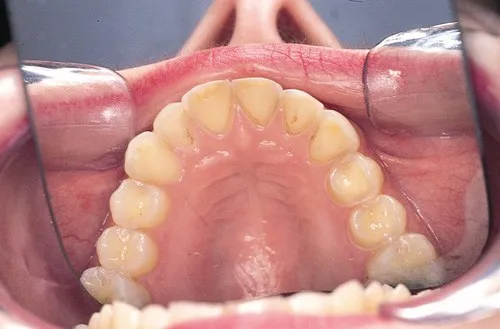

- Dental enamel erosion (lingual surfaces).

- Dental:

- Enamel erosion (perimylolysis, especially lingual surfaces)

- Increased dental caries, periodontitis